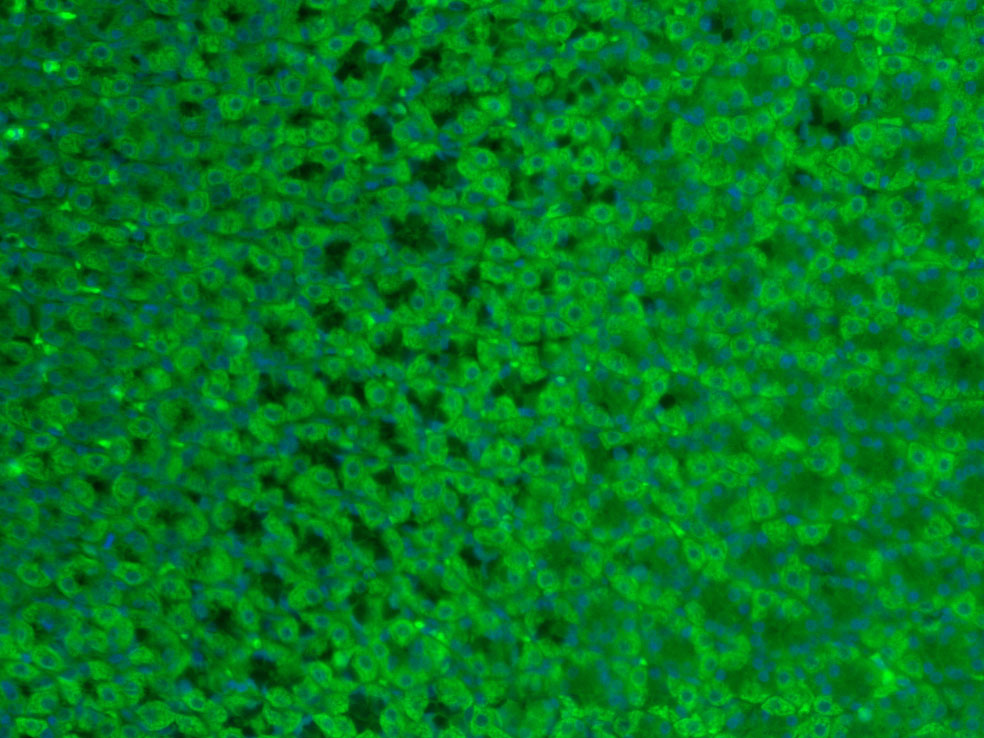

| 产品应用 | IHC-P=1:100-500, IHC-F=1:100-500, IF=1:200-800 Not yet tested in other applications. |

| {IF} | {1:200-800} |

Antigen retrieval: citrate buffer ( 0.01M, pH 6.0 ), Boiling bathing for 15min; Block endogenous peroxidase by 3% Hydrogen peroxide for 30min; Blocking buffer (normal goat serum,C-0005) at 37℃ for 20 min;

Incubation: Anti-GLP-2 Polyclonal Antibody, Unconjugated(bs-0208R) 1:200, overnight at 4°C, followed by conjugation to the secondary antibody(SP-0023) and DAB(C-0010) staining